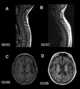

Progressive brain atrophy

Cerebral atrophy is a common feature of many of the diseases that affect the brain. Atrophy of any tissue means a decrement in the size of the cell, which can be due to progressive loss of cytoplasmic proteins. [Source: Wikipedia ]